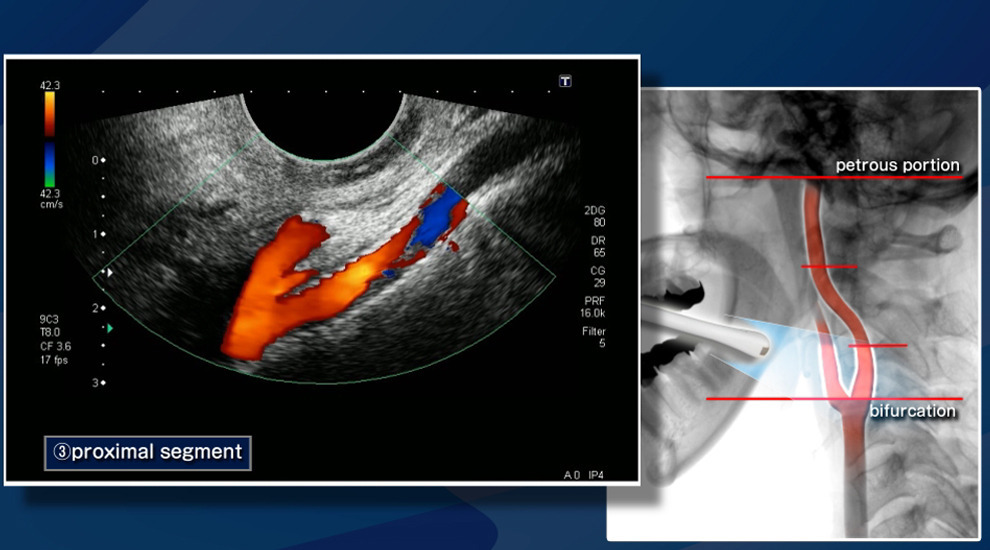

경동맥 초음파 검사는 목을 지나는 주요 혈관인 경동맥(Carotid artery)의 상태를 정밀하게 확인할 수 있는 비침습적 영상 검사입니다. 경동맥은 뇌로 혈액을 공급하는 가장 중요한 혈관 중 하나이기 때문에 이곳에 문제가 생기면 뇌졸중(뇌경색, 뇌출혈), 일과성 허혈발작(TIA) 등 생명과 직결되는 질환으로 이어질 수 있습니다. 초음파를 이용하는 방식이라 방사선 노출이 없고, 시술 절차가 간단하며, 통증이 거의 없기 때문에 심뇌혈관질환 예방의 핵심 검진으로 각광받고 있습니다.

경동맥 초음파는 혈관 벽과 혈류를 실시간 영상으로 관찰할 수 있어 여러 질환을 조기에 파악하는 데 유용합니다. 확인 가능한 대표 적인 경동맥 초음파 검사로 알수있는병은 다음과 같습니다.

- 젤을 바른 후 초음파 탐촉자를 경동맥 위에 대고 영상 관찰

- 혈류 속도 측정과 플라크 유무 확인